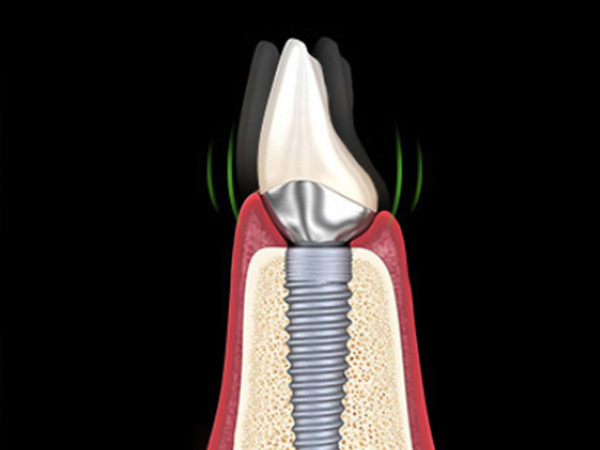

임플란트 주위 뼈가 녹았거나 임플란트 자체가 파손된 경우도 있습니다.

반대로 임플란트 주변 뼈가 심하게 녹았거나 나사가 부러진 경우에는 살리기보다 제거와 재수술이 더 안전할 수 있습니다.

임플란트 주변이 자주 붓거나 통증이 반복되고, 양치 후 피가 나거나 잇몸이 자꾸 붉게 부어오르는 경우 재수술을 고려할 수 있습니다.

씹을 때 임플란트가 흔들리거나, 엑스레이 상에서 뼈가 많이 녹아 있는 것이 확인될 때에도 추가 치료 또는 재수술이 필요할 수 있습니다.

나사 풀림, 나사 파절, 보철물이 반복적으로 깨지는 경우에는 구조적인 문제를 동반한 경우가 많아, 단순 수리보다 재계획이 중요합니다.